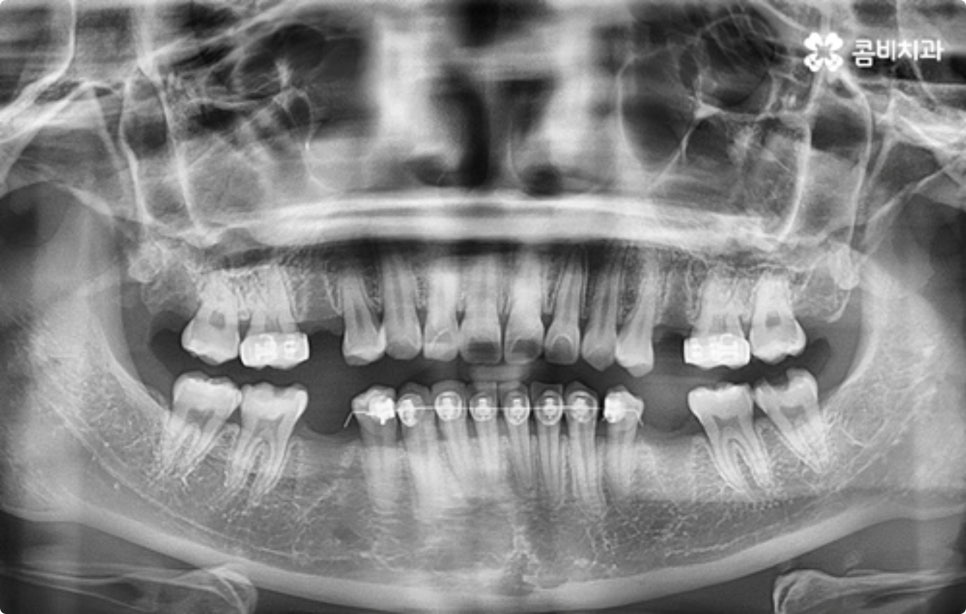

클리피씨 교정도 치아 색상의 세라믹 재질을 사용하기 때문에 심미성이 높은 편이지만 만약에 장치가 아예 겉으로 드러나지 않았으면 좋겠다고 생각하신다면 브라켓을 치아 안쪽에 부착하는 설측교정을 이용할 수 있는데요. 하지만 설측교정은 혀와 맞닿는 부분의 이물감, 통증, 발음상 문제 등을 일으킬 수 있기 때문에 잘 보이는 윗니는 설측으로, 잘 드러나지 않는 아랫니는 보통 교정과 같이 순측 (입술쪽) 으로 진행하는 콤비교정을 통해 이를 보완할 수 있어요. 사진에서 살펴보실 수 있는 케이스 역시 이렇게 콤비로 진행한 직장인치아교정 과정으로 시간이 지날수록 점차 치열이 가지런해지고 교합이 올바르게 개선되는 것을 확인해 보실 수 있습니다.